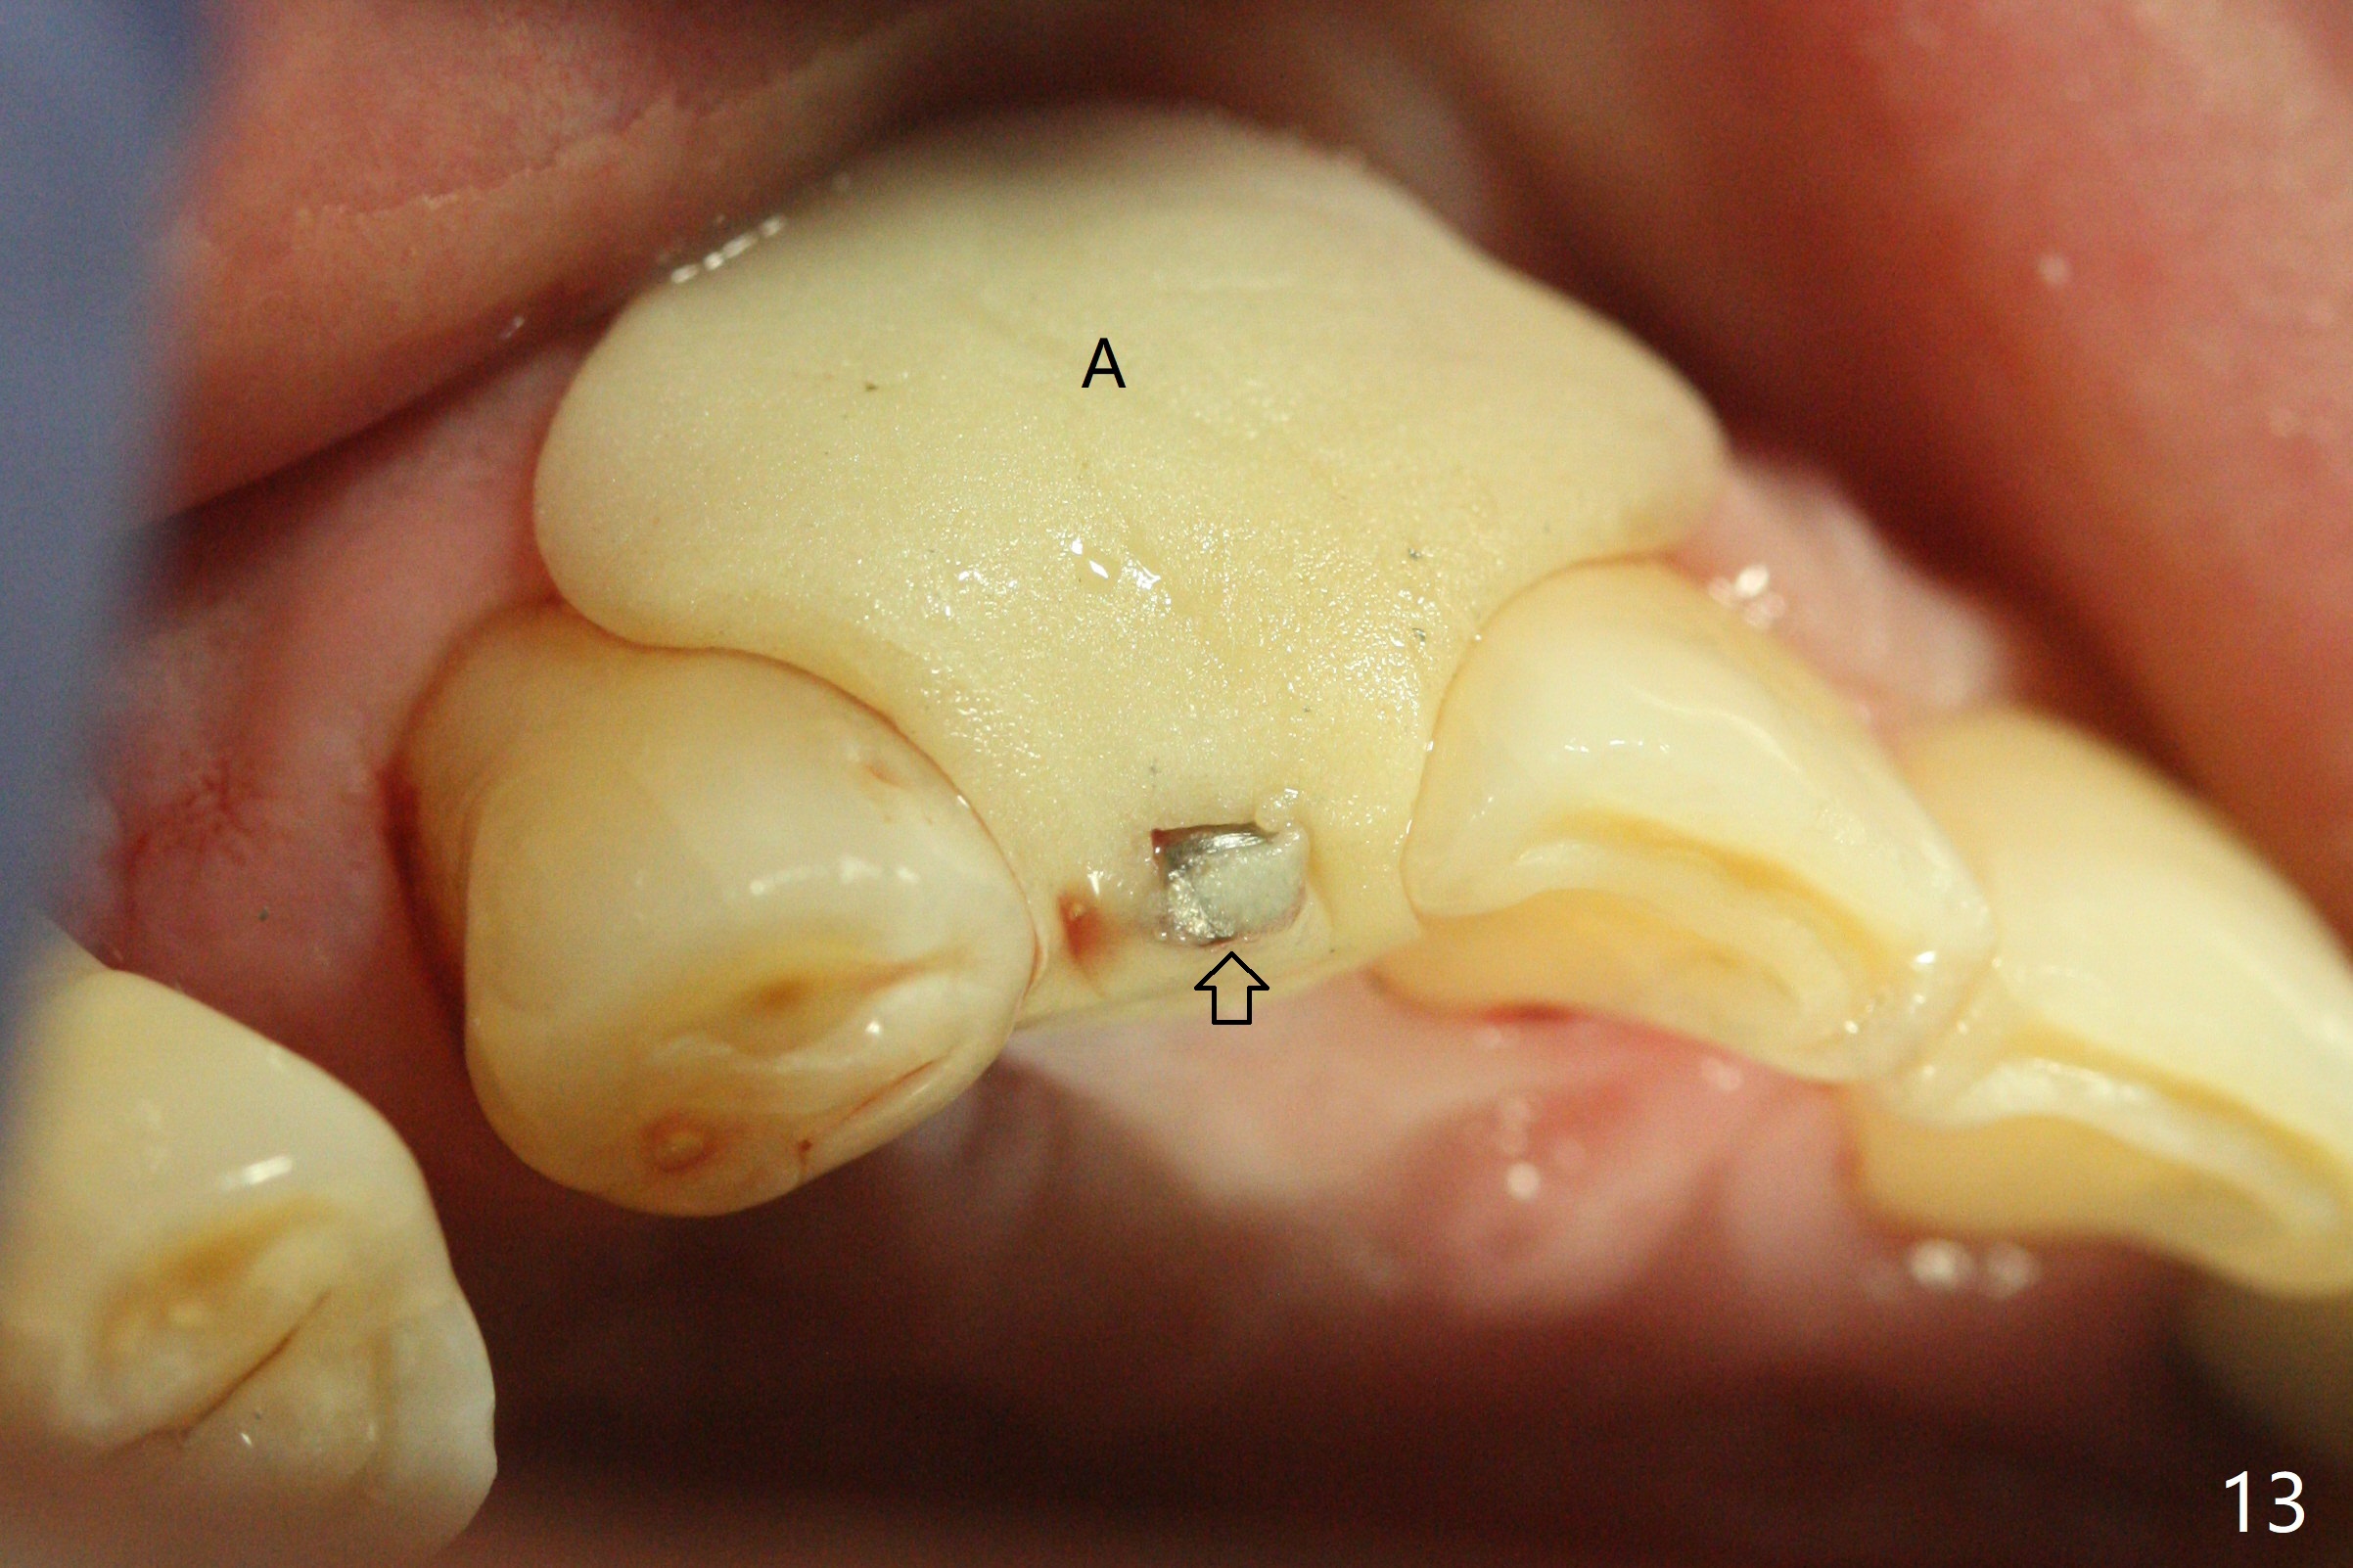

68岁男士右上2严重骨质吸收,颊侧骨板缺失,术前牙龈退缩也十分明显(图一,二),术中对脆弱牙龈缘(图三:*)不应施加任何压力或者牵拉,更不能切开,保持最佳血供。按照术前设计,在牙槽窝腭侧钻洞(图四),植入2.5x15毫米一段式植体(扭力>35Ncm),基台特长(牙龈厚,图五)),基台位于合适修复位置(图六),4-5毫米螺纹颊侧暴露(图七:*)。植骨(图八(CT冠状切面(拔牙后:黑色)):箭头)前,将PRF膜(白线)一头(a)插入牙槽窝颊侧,另外一头(图八,九:b)放置颊侧牙龈颊侧。然后填入粘性骨粉(图九:S;图十四:*),将b头PRF膜往下翻,它末端事先冲一个洞(punch a hole using sterilized rubber dam punch),插入基台(图十(粉红色),十一),这样PRF膜不移位,牢靠地固定骨粉(图十(红圆圈),图十四:*),最后使用树脂敷料覆盖伤口(图十二,十三:A),同样需要基台(箭头,也就是一段式植体)固定,也就是没有即刻植体,就没有骨粉固位。术后两个月伤口缩小,肉芽组织生长(图十五)。撤除树脂敷料后,制作临时牙冠,半个月后唇侧植体有些暴露(图十六),嘱咐强化口腔卫生。